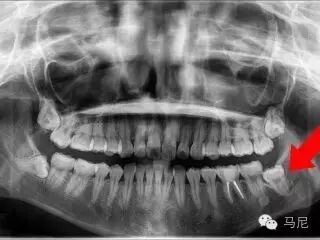

拔牙前的风险和难度预判非常重要。术者需要在拔牙前应针对病人主诉问题进行详细口内检查、仔细确认所需拔除的牙齿,了解患牙情况及其与邻牙、周围组织的关系。所有患者常规均应行术前X线片检查,对于根尖片无法满足手术需要的病例,则需进一步拍摄牙科CT,了解牙齿形态、结构及与周围重要解剖结构(如上颌窦、下颌神经管等)的位置关系。术前与患者及家属进行良好的交流和沟通,交代拔牙术过程及术中、术后的相关事项,以缓解患者的紧张、恐惧心理,取得其信任与配合。对于高度紧张或牙科恐惧症患者,术前应采用镇痛、镇静等措施,以达到心理、精神的微创。此外,根据术前预判和设计,准备合适的微创拔牙器械。

3,去骨与增隙

去骨本身违反微创的原则,但在许多情况(如完全骨埋伏的牙)下却是不可避免的。去骨的目的在于显露牙齿变埋伏牙为暴露牙,增隙并解除拔牙时骨阻力。去骨需遵循微创原则:应尽量少去骨;尽量保持皮质骨高度、宽度和厚度。去骨部位和去骨量应根据X线片和临床实际的牙体周围骨质覆盖状况而定。去骨可采用外科专用切割手机和钻针进行。推荐车针是马尼M15EZ,M15ZB。这两款车针可以作为去骨增隙用车针,直径为1.5mm,符合增隙要求。特别是M15ZB,最适合去骨,而且可以用来切割牙冠与牙根,但是要注意切割时不要用力撬动车针。要用轻点触法尽量减少对组织的压力,严格控制车针的转速(定期检查牙椅,防止牙椅气压异常也是个控制转速的必要工作)。